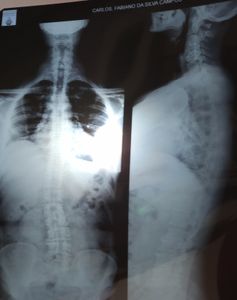

Me chamo Carlos Fabiano da S. Campos, tenho 48 anos e fui diagnosticado com uma doença Crônica Degenerativa Autoimune, chamada Espondilite Anquilosante.

As minhas dores começaram no ano de 2001, mas foi apenas em 2021, que descobriram essa doença grave, crônica, incurável, sistêmica, extremamente limitante. Uma enfermidade extremamente dolorosa a ponto de requerer o uso de Morfina, desumanamente progressiva, levando à degenerações precoces que acometem todo o eixo esquelético Axial e Periférico. Podendo destruir coluna, punhos, cotovelos, ombros, quadris, joelhos, tornozelos, calcanhares e pés. Podendo ocasionar sérias deformidades que  requerem cirurgias. Promove também perda parcial ou total da visão com uma inflamação chamada Uveíte. CIRURGIAS REALIZADAS: Pé esquerdo (placa e parafusos); Artroplastia do Ombro esquerdo. CIRURGIAS EM PRÉ-OPERATÓRIOS : Olho esquerdo (Uveíte); Coluna Lombar. CIRURGIAS PROGRAMADAS ATÉ O FINAL DE 2023: Pé direito (placa e parafusos); Artroplastia do Ombro direito. Até o momento são essas, mas a Espondilite Anquilosante é uma caixinha de segredo.